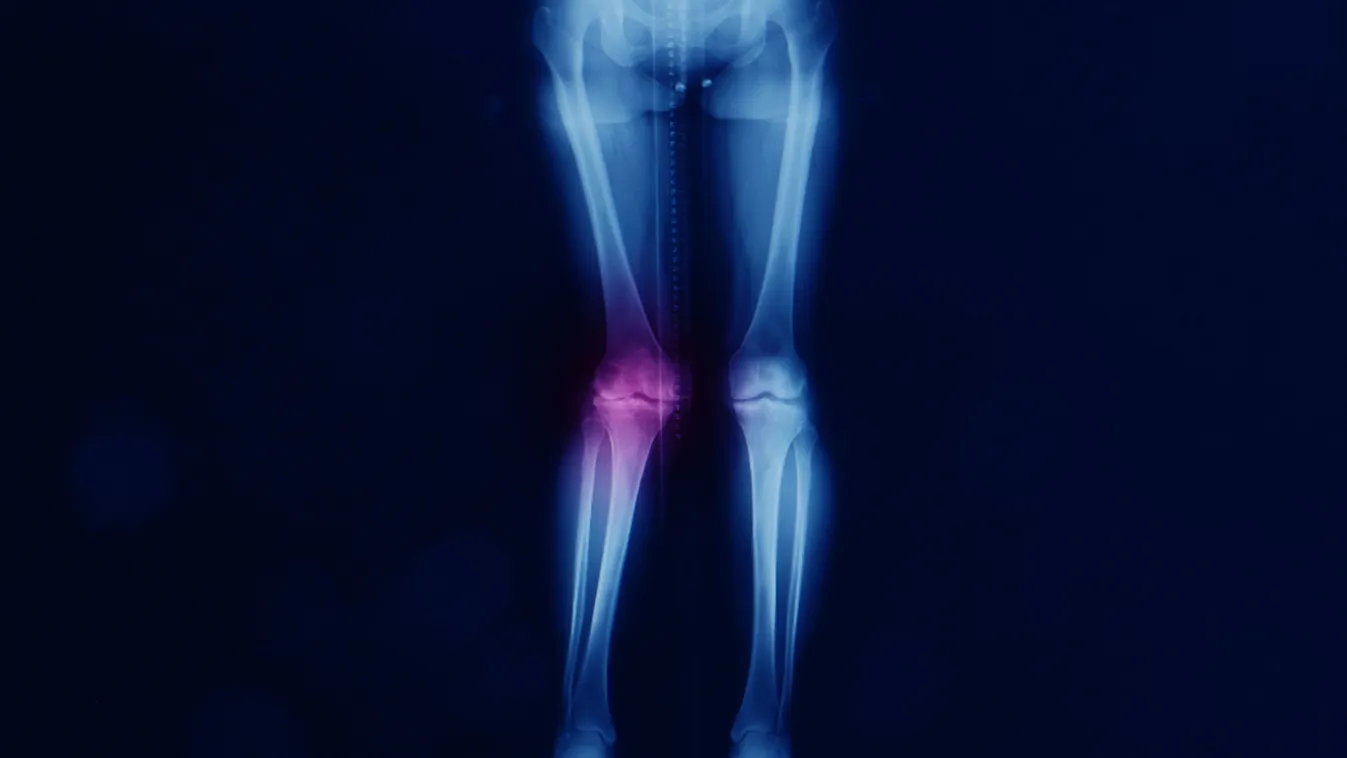

Az X-lábúság, tudományos nevén a valgus lábállás során az alsó végtag tengelye befelé tér el, ami leggyakrabban a térdek összeérésében nyilvánul meg. Miközben a térdek közelítenek egymáshoz, a bokák között nagyobb távolság marad. Ez az eltérés megváltoztatja a testsúly eloszlását járás és állás közben.

A szakértők szerint a valgus lábállás hosszú távon fokozott terhelést ró a térd belső és külső részeire, ami ízületi kopáshoz vezethet.